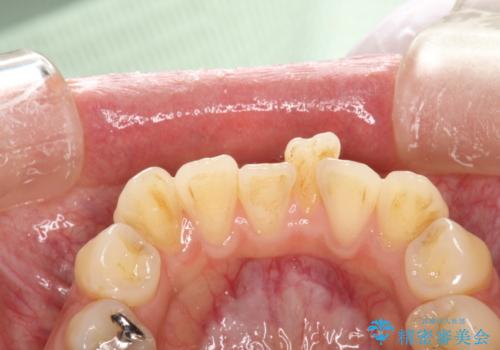

- 矯正前にしっかりとクリーニングを行いたいとのことで来院されました。PMTC30分コースを行いました。

プラーク(細菌の塊)や歯石がたまると歯の表面はザラつきいてきます。そのザラつきは歯周病や虫歯菌の棲家となります。そのまま放置すると、歯肉が腫れてきたり、歯肉から出血したり、口臭が強くでたりします。とくに歯肉の境目は、歯磨きで汚れを除去することが難しく、プラーク(細菌の塊)や歯石が溜まりやすい場所です。

歯並が、がたついている場合はなおさら汚れが溜まりやすいです。矯正治療前や定期的にPMTCをすることで、矯正治療中の歯肉トラブルを防ぐことにつながります。